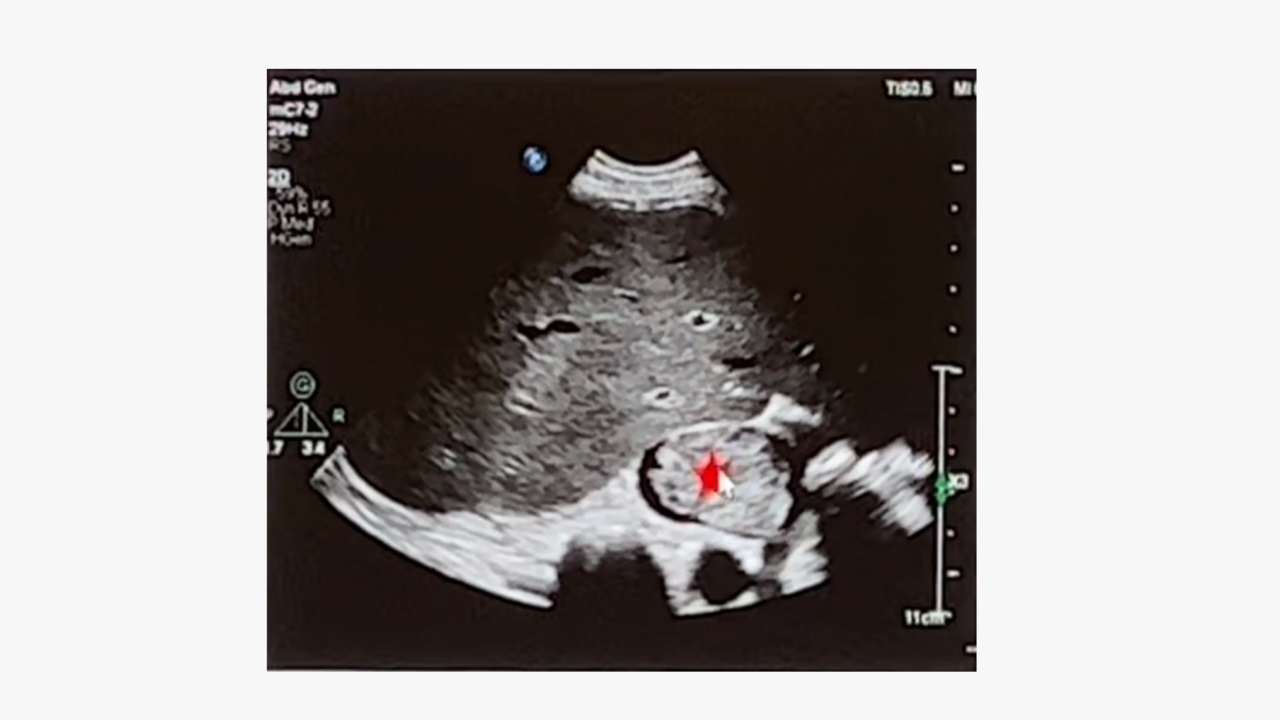

盆腔CT:显示子宫右侧有造影剂强化的结节,盆腔肿物由于血管丰富呈明显不规则强化,可推挤膀胱向右前方移位。

CTA:显示静脉内平滑肌瘤起源于左侧宫旁,沿着左侧髂内静脉、髂总静脉、下腔静脉一直延伸到右心房。